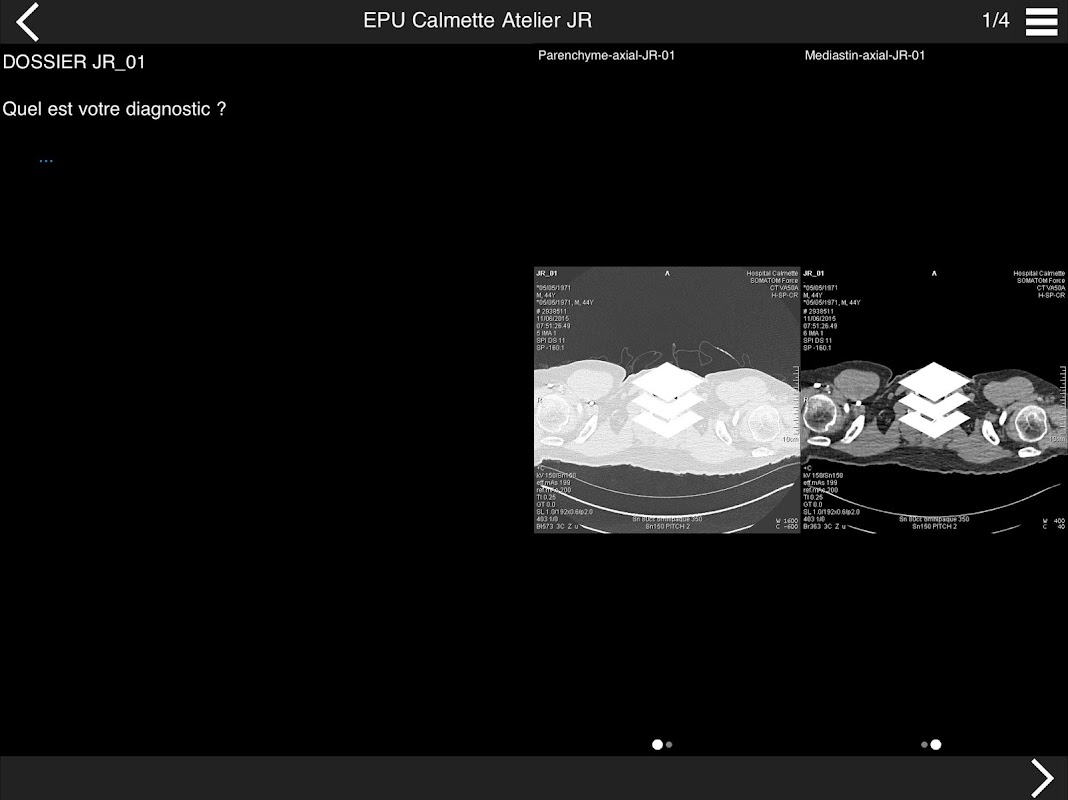

Retrouvez les cas cliniques du Cours intensif de TDM multicoupe du thorax dans cette application.

Thèmes du cours 2017 :

• DE LA SéMIOLOGIE AU COMPTE-RENDU

* BPCO et nodules pulmonaires : recommandations en 2017

* Pathologie interstitielle : lésions élémentaires et « patterns »

* Pathologie vasculaire et médiastinale

* Oncologie thoracique : bilan standard et introduction à l’étude de l’angiogénèse